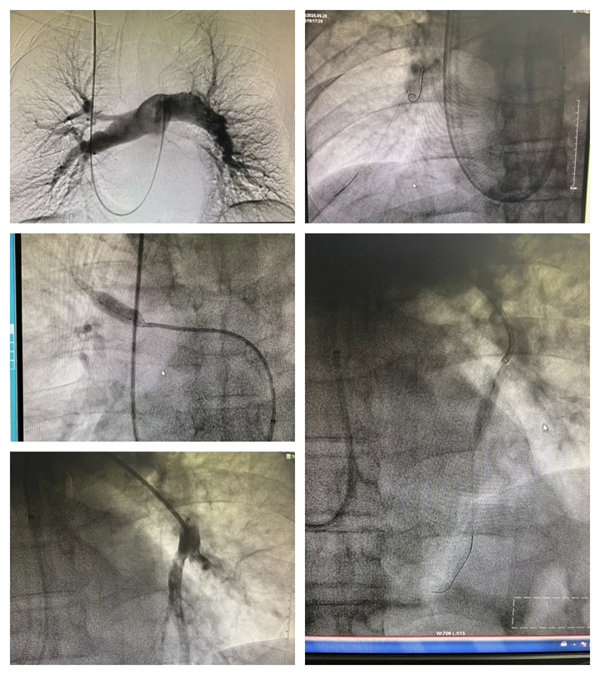

近日,寶雞市人民醫院心血管內一科成功為一名慢性血栓栓塞性肺動脈高壓患者實施右心導管測壓+肺動脈造影+肺動脈球囊擴張成形術,該手術的成功開展,填補了我院心血管內科此項技術的空白,進一步完善了心血管內一科在肺動脈高壓領域的長時程治療管理體系,為慢性血栓栓塞性肺動脈高壓患者帶來了新的治療選擇。

心血管內一科醫護團隊一致認為患者需行右心導管測壓、肺動脈造影、肺動脈球囊擴張術。與患者及家屬詳細溝通后,同意手術治療。術前準備就緒后,在西安交通大學第一附屬醫院張松林教授指導下,心血管內一科主任翟向偉、副主任醫師陳萬林及介入導管室團隊密切配合,順利完成手術。因患者之前植入的下腔靜脈濾器未取,手術團隊穿刺右側頸內靜脈經導管測平均肺動脈壓力50mmHg(重度),進一步行肺動脈造影提示患者雙側肺動脈多發嚴重狹窄,部分肺動脈閉塞。介入團隊隨后依次對左右肺動脈狹窄病變進行球囊擴張成形術(共擴張肺動脈5支),術后患者胸悶氣短癥狀明顯減輕。經過醫護團隊的精細治療及護理,患者順利出院。擇期將再次行肺動脈球囊擴張術。